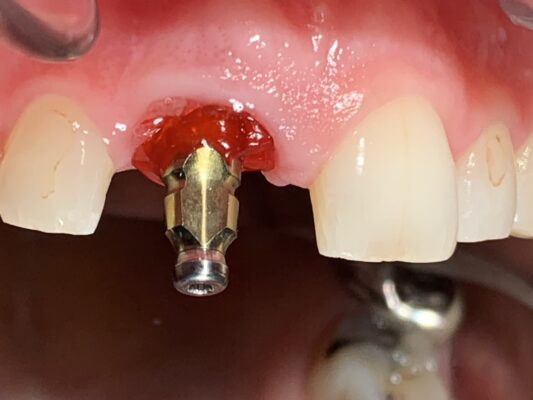

Simultaneous immediate implant placement and GBR (guided bone regeneration) utilizing CGF/PRF protocols on tooth #9 due to a failing root canal that destroyed the facial plate.

Reentry was between 5 and 6 months right after CBCT was taken and shortly after the site was restored. Upper right central incisor was crowned when the upper left…